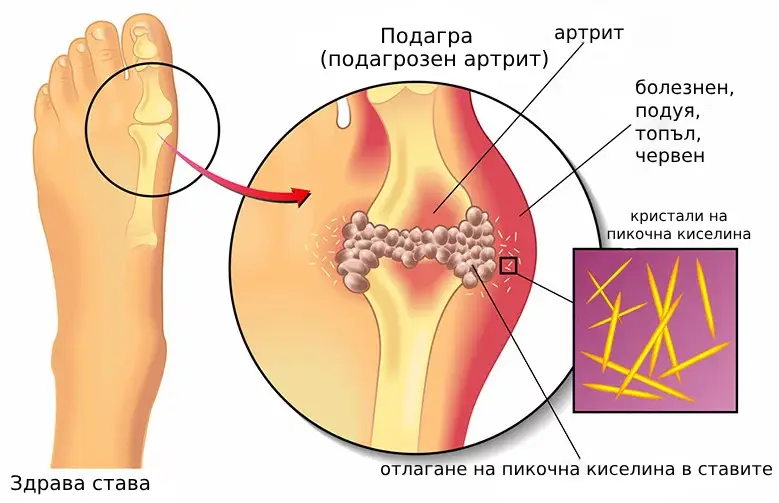

Група хора (1000 души) със ставни заболявания с различна етиология приемаха Hondro Sol всеки ден в продължение на месец в болница в България.

По време на тестовете бяха получени следните резултати:

Облекчаване на болки в ставите-98%

Значително подобрение на подвижността на ставите-96%

Намаляване на подпухналостта-97%

Елиминиране на възпалителния процес-96%

Доказано е, че Hondro Sol има мощен ефект за подобряване на подвижността на ставите и производството на синовиална течност. Той е показан за пациенти със ставни заболявания като артроза, ревматоиден артрит, остеохондроза, остеопороза, подагра и много други патологии.

Това е уникално развитие на Института за клинични изследвания в България. Hondro Sol е комплекс от редки естествени компоненти, подбрани в правилните пропорции, които

активират клетъчните процеси на регенерация и обновяване на ставните тъкани.

Д-р Кристиян Гоновски: Да, това е той. Този спрей съдържа много мощна и рядка съставка-Арника

Монтана. Тази съставка е в състояние да увеличи производството на

синовиална течност със 70% и няколко пъти да ускори регенерацията на тъканите на клетъчно

ниво.

Д-р Кристиян Гоновски: Да, това е той. Този спрей съдържа много мощна и рядка съставка-Арника

Монтана. Тази съставка е в състояние да увеличи производството на

синовиална течност със 70% и няколко пъти да ускори регенерацията на тъканите на клетъчно

ниво.

С прилагането на курса процесът на дегенерация и разрушаване на ставата ще бъде спрян и ще започне процесът на възстановяване на тъканите.

В допълнение, Hondro Sol съдържа Boswellia Serrata и Cupressus sempervirens. Първият компонент има мощен аналгетичен ефект и бързо облекчава възпалението, а вторият подобрява кръвообращението в ставната торбичка, увеличава подвижността, предотвратява абразията и предпазва от свързани с възрастта промени в ставната тъкан.

По този начин имаме мощна формула, която може бързо и ефективно да възстанови способността за активен начин на живот.